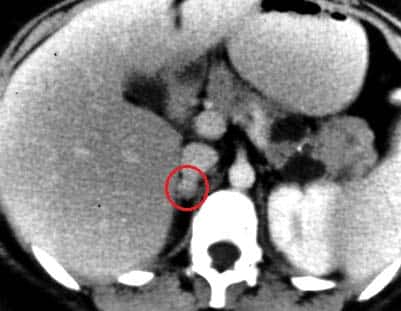

The adrenal (or suprarenal) glands are paired endocrine glands situated over the medial aspect of the upper poles of each kidney. They secrete steroid and catecholamine hormones directly into the blood. In this article, we shall look at the anatomy of the adrenal glands – their location, structure and vascular supply. By TeachMeSeries Ltd (2025) Fig 1The right adrenal gland, situated over the medial aspect of the upper pole of the right kidney. Pro Feature - 3D Model You've Discovered a Pro Feature Access our 3D Model Library Explore, cut, dissect, annotate and manipulate our 3D models to visualise anatomy in a dynamic, interactive way. Learn More Anatomical Location and Relations The adrenal glands are located in the posterior abdomen, between the superomedial kidney and the diaphragm. They are retroperitoneal structures, with parietal peritoneum covering their anterior surface only. The right gland is pyramidal in shape, contrasting with the semi-lunar shape of the left gland. Perinephric (or renal) fascia encloses the adrenal glands and the kidneys. This fascia attaches the glands to the crura of the diaphragm. They are separated from the kidneys by a small amount of fibrous tissue. The adrenal glands sit in close proximity to many other structures in the abdomen: Right adrenal gland Left adrenal gland Anterior Posterior Anterior Posterior Inferior vena cava Right lobe of the liver Right crus of the diaphragm Stomach Pancreas Spleen Left crus of the diaphragm By TeachMeSeries Ltd (2025) Fig 2Posterior view of the abdomen, demonstrating the anatomical relations of the adrenal glands. Pro Feature - Dissection Images Dissected kidney and associated adrenal gland, posterior view. Note the prescence of an aberrant renal artery. Dissected kidney and associated adrenal gland, posterior view. Note the prescence of an aberrant renal artery. You've Discovered a Pro Feature Access our Dissection Image Library Enhance your understanding with high-resolution dissection images showcasing real-life anatomy. Learn More Anatomical Structure The adrenal glands consist of an outer connective tissue capsule, a cortex and a medulla. Veins and lymphatics leave each gland via the hilum, but arteries and nerves enter the glands at numerous sites. The outer cortex and inner medulla are the functional portions of the gland. They are two separate endocrine glands, with different embryological origins: Cortex – derived from the embryonic mesoderm. Medulla – derived from the ectodermal neural crest cells. The cortex and medulla synthesise different hormones. Cortex The cortex is yellowish in colour. It secretes two cholesterol derived hormones – corticosteroids and androgens. Functionally, the cortex can be divided into three regions (superficial to deep): Zona glomerulosa – produces and secretes mineralocorticoids such as aldosterone. Zona fasciculata – produces and secretes corticosteroids such as cortisol. It also secretes a small amount of androgens. Zona reticularis – produces and secretes androgens such as dehydroepiandrosterone (DHES). It also secretes a small amount of corticosteroids. By TeachMeSeries Ltd (2025) Fig 3Histological appearance of the cortex and medulla of the adrenal gland. Medulla The medulla lies in the centre of the gland, and is dark brown in colour. It contains chromaffin cells, which secrete catecholamines (such as adrenaline) into the bloodstream in response to stress. These hormones produce a ‘flight-or-fight‘ response. Chromaffin cells also secrete enkephalins which function in pain control. Vasculature The adrenal glands have a rich blood supply via three main arteries: Superior adrenal artery – arises from the inferior phrenic artery Middle adrenal artery – arises from the abdominal aorta. Inferior adrenal artery – arises from the renal arteries. Right and left adrenal veins drain the glands. The right adrenal vein drains into the inferior vena cava, whereas the left adrenal vein drains into the left renal vein. Innervation The adrenal glands are innervated by the coeliac plexus and greater splanchnic nerves. Sympathetic innervation to the adrenal medulla is via myelinated pre-synaptic fibres, mainly from the T10 to L1 spinal cord segments. Lymphatics Lymph drainage is to the lumbar lymph nodes by adrenal lymphatic vessels. These vessels originate from two lymphatic plexuses – one deep to the capsule, and the other in the medulla. Clinical Relevance Pheochromocytoma A pheochromocytoma is a tumour of the adrenal medulla or preganglionic sympathetic neurones. It secretes adrenaline and noradrenaline uncontrollably, causing blood pressure to greatly increase. Patients may present with palpitations, headaches and diaphoresis (profuse sweating). Phenoxybenzamine, a competitive, irreversible antagonist of adrenaline, can be used in treatment to reduce blood pressure by binding to adrenaline receptors, making less available for adrenaline to act upon. By TeachMeSeries Ltd (2025) Fig 4CT scan of a pheochromocytoma. Do you think you’re ready? Take the quiz below Pro Feature - Quiz The Adrenal Glands Question 1 of 3 Submitting... Skip Next Rate question: You scored 0% Skipped: 0/3 1800 More Questions Available Upgrade to TeachMeAnatomy Pro Challenge yourself with over 1800 multiple-choice questions to reinforce learning Learn More Rate This Article